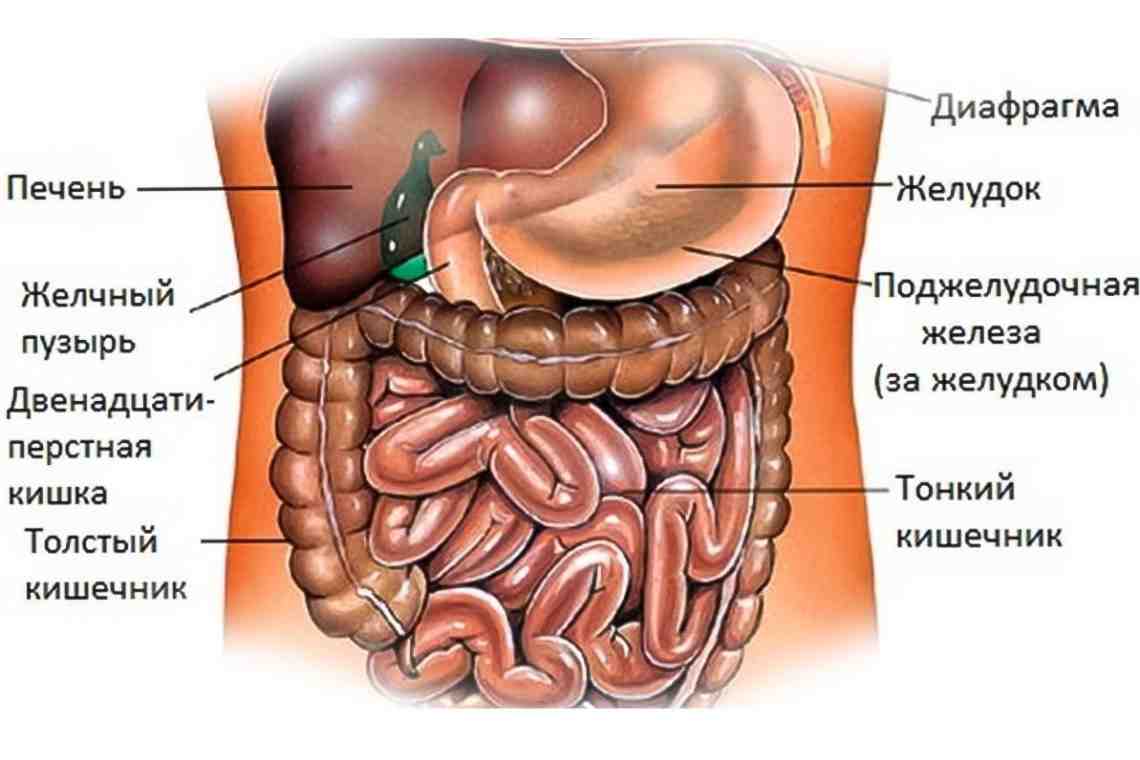

Изображения и визуализация внутренних органов человека